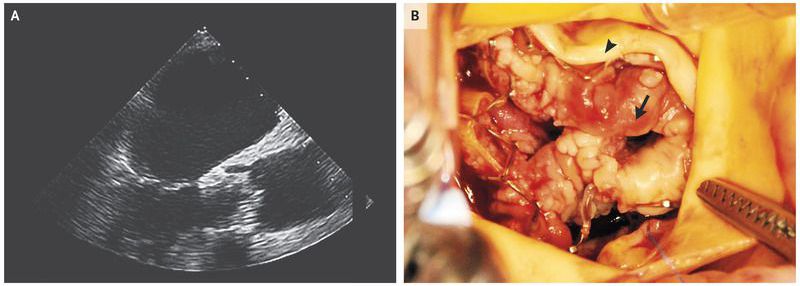

A 76-year-old man with a history of congestive heart failure and an ejection fraction of 45% presented to the emergency department with worsening shortness of breath. He had undergone transcatheter aortic-valve replacement (TAVR) 9 months earlier. His temperature was 39.0°C, and a grade 5 systolic murmur (associated with a palpable thrill) was detected on cardiac examination. A chest radiograph showed changes consistent with pulmonary edema. Laboratory results were notable for a white-cell count of 16,000 cells per cubic millimeter (reference range, 4000 to 10,000) and a C-reactive protein level of 120 mg per liter (reference range, <5). Six consecutive blood cultures were positive for Candida parapsilosis. Treatment with antifungal agents was initiated. Prosthetic-valve endocarditis was confirmed on transesophageal echocardiography , which revealed a large vegetation causing substantial obstruction of the prosthetic valve (transvalvular mean pressure gradient, 52 mm Hg; aortic-valve area, 0.5 cm2). Surgical aortic-valve replacement was performed, and the vegetation (Panel B, arrow) and the native leaflet (Panel B, arrowhead) were visualized. The postoperative course was complicated by wound infection at the surgical site. The patient was discharged but was readmitted 4 weeks later with pneumonia. He died from an aspiration event after a 2-month hospitalization.